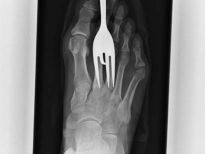

Bu röntgenler gerçek!

Bu röntgenler gerçek! galerisi resim 1